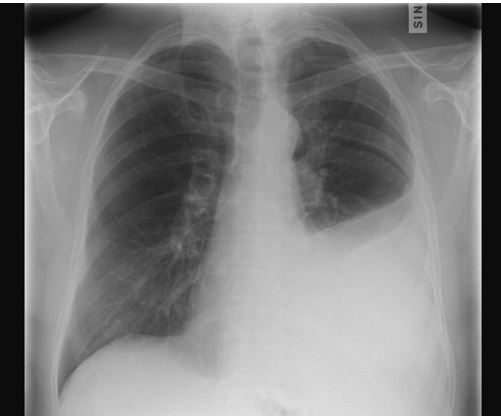

Man kan använda pleurapunktion för att ställa en diagnos, men man kan också göra den för att lindra andnödssymtom. Undersökningen görs med ultraljudsstyrning. Med ultraljudet ser läkaren var vätskan finns och hur mycket det finns. Läkaren lokaliserar rätt injektionsställe och tömmer den överflödiga vätskan ur lungsäcken med en spruta.

Ingreppet är säkert och utsätter inte patienten för strålning. Vid behov gör man en kontrollthoraxröntgen efter ingreppet. En mycket sällsynt komplikation vid pleurapunktion är lungkollaps eller blödning.